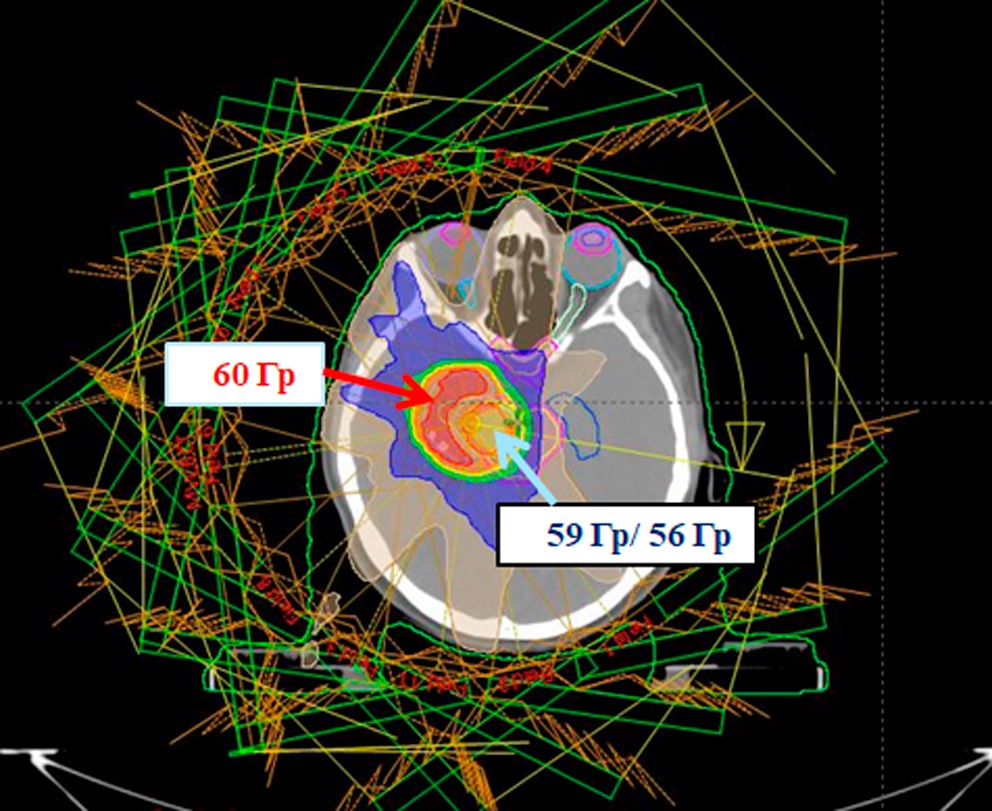

Итоговый план, реализованный на ускорителе электронов Halcyon (Varian) с энергией фотонов 6 МВ, содержит 11 полей IMRT (Intensity Modulated Radiation Therapy) (рис. 2, 3).

Рисунок 2. Объемы облучения: область ствола (59 Гр/эмпирически 56 Гр): mp_PTV56, mp_GTV56 (голубая стрелка) и пораженная область вне стволовой локализации (60 Гр) mp_PTV60, mp_GTV60 (красная стрелка); красным цветом обозначена область, получающая 60 Гр, оранжевым — 59 Гр, желтым — 56 Гр, зеленым — 44,8 Гр (80 % от 56 Гр), синим — 28 Гр (50 % от 56 Гр)

Figure 2. Irradiation volumes: stem area (59 Gy/empirically 56 Gy): mp_PTV56, mp_GTV56 (blue arrow) and the affected area outside the stem localization (60 Gy) mp_PTV60, mp_GTV60 (red arrow); red indicates the area receiving 60 Gy, orange — 59 Gy, yellow — 56 Gy, green — 44.8 Gy (80 % of 56 Gy), blue — 28 Gy (50 % of 56 Gy)

В результате планирования удалось выполнить критерии для ствола мозга и PRV объема ствола мозга (рис. 4): максимальная доза в точке для ствола мозга не превышает 59 Гр, для PRV объема ствола мозга — меньше 60 Гр.